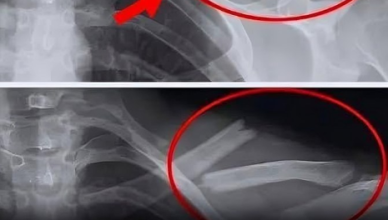

Zdjęcie rentgenowskie ujawniło setki złotych igieł w kolanach kobiety

Kiedy lekarze zbadali zdjęcie rentgenowskie kolan starszej kobiety cierpiącej na silne bóle stawów, odkryli prawdziwą żyłę złota: setki maleńkich złotych igieł do akupunktury